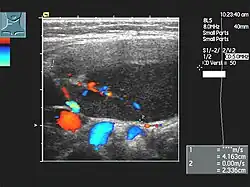

- Sonographie des Bauchraums